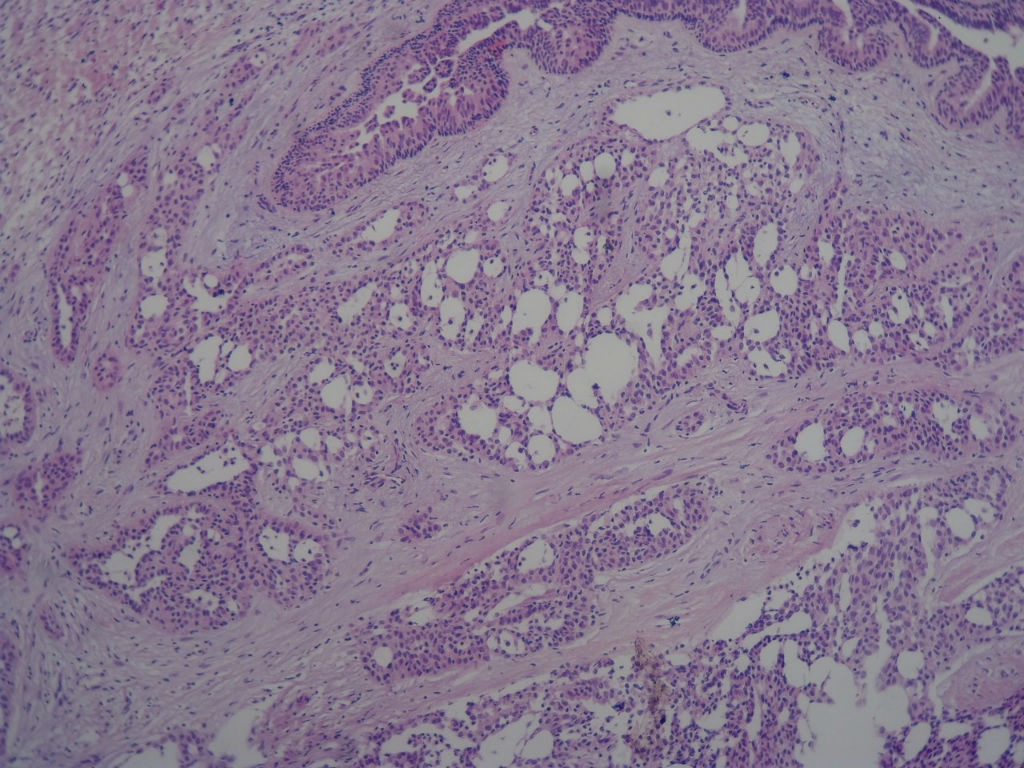

癌是以侵袭性生长和复发转移为特征的,镜下表现为组织结构的紊乱、细胞的异型性,乳腺冰冻病理的诊断要从大体、镜下组织学表现、细胞形态等方面做出综合判断。组织学形态着重看有无正常结构的消失、是否存在浸润性生长的特征,本例冰冻中看不到小叶结构特征,腺管大小、排列比较杂乱。部分不规则的小腺体围绕正常导管生长,这是否应是浸润的一种表现。细胞学上冰冻切片的细胞异型的判断一般认为是不可靠的,但在切片质量较好,有内对照的参考标尺下还是可以判读的,正常的导管上皮是一把可以利用的标尺。这一例我们结合病人年龄、大体、镜下表现术中报癌了,上级医院会诊标记肌上皮已证实是癌,以后会把相关免疫组化补上。但现在想来这例报癌风险还是很大的,有点后怕,以后在遇到可能会后退一步,也许是不认识类似的硬化性腺病吧,当时做术中诊断有点应了一句话:无知者无畏。

会诊结果:乳腺分泌型癌。免疫组化:ER(-), PR(-), CerbB-2(-) Ki67阳性率约10%,S-100(+),CEA灶性阳性,P63、SMA肌上皮阴性,CK5/6肿瘤上皮细胞阴性,CK34BE12部分阳性。

本例太完美了,也非常惊险,真的,至少在我们中国的这个病理环境下能做到这样真心不错。这是个罕见病例,居然冰冻让你碰上了,从冰冻——常规——IHC都完备。我从冰冻看到常规未看免疫组化之前还一直犹豫是不是癌?是癌但一定是您说的分泌性癌吗?看常规时只是觉得浸润性癌够了,后来看到常规的筛状结构+分泌物才确定形态学也够了,就差IHC了,结果您贴出来上级医院的IHC结果真的是3阴,S-100+,高分子量CK部分+,这个表达模式完全符合分泌性癌(我也遇到一个分泌性癌,IHC表达方式完全和您的这例一样),当然必须是结合形态学了。